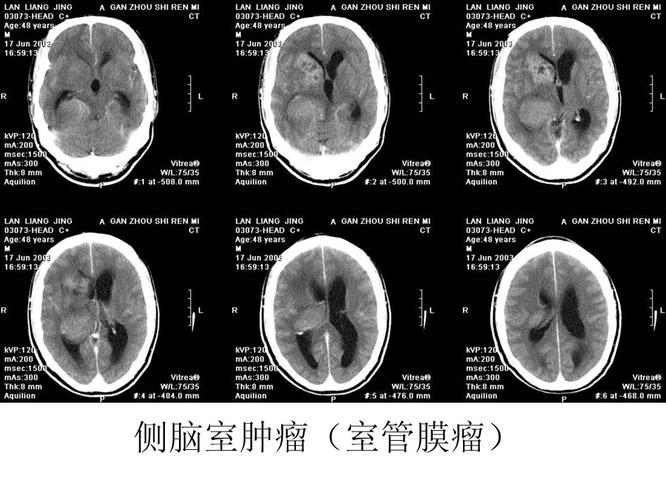

室管膜瘤(侧脑室,双侧,右侧为主,左侧囊变)